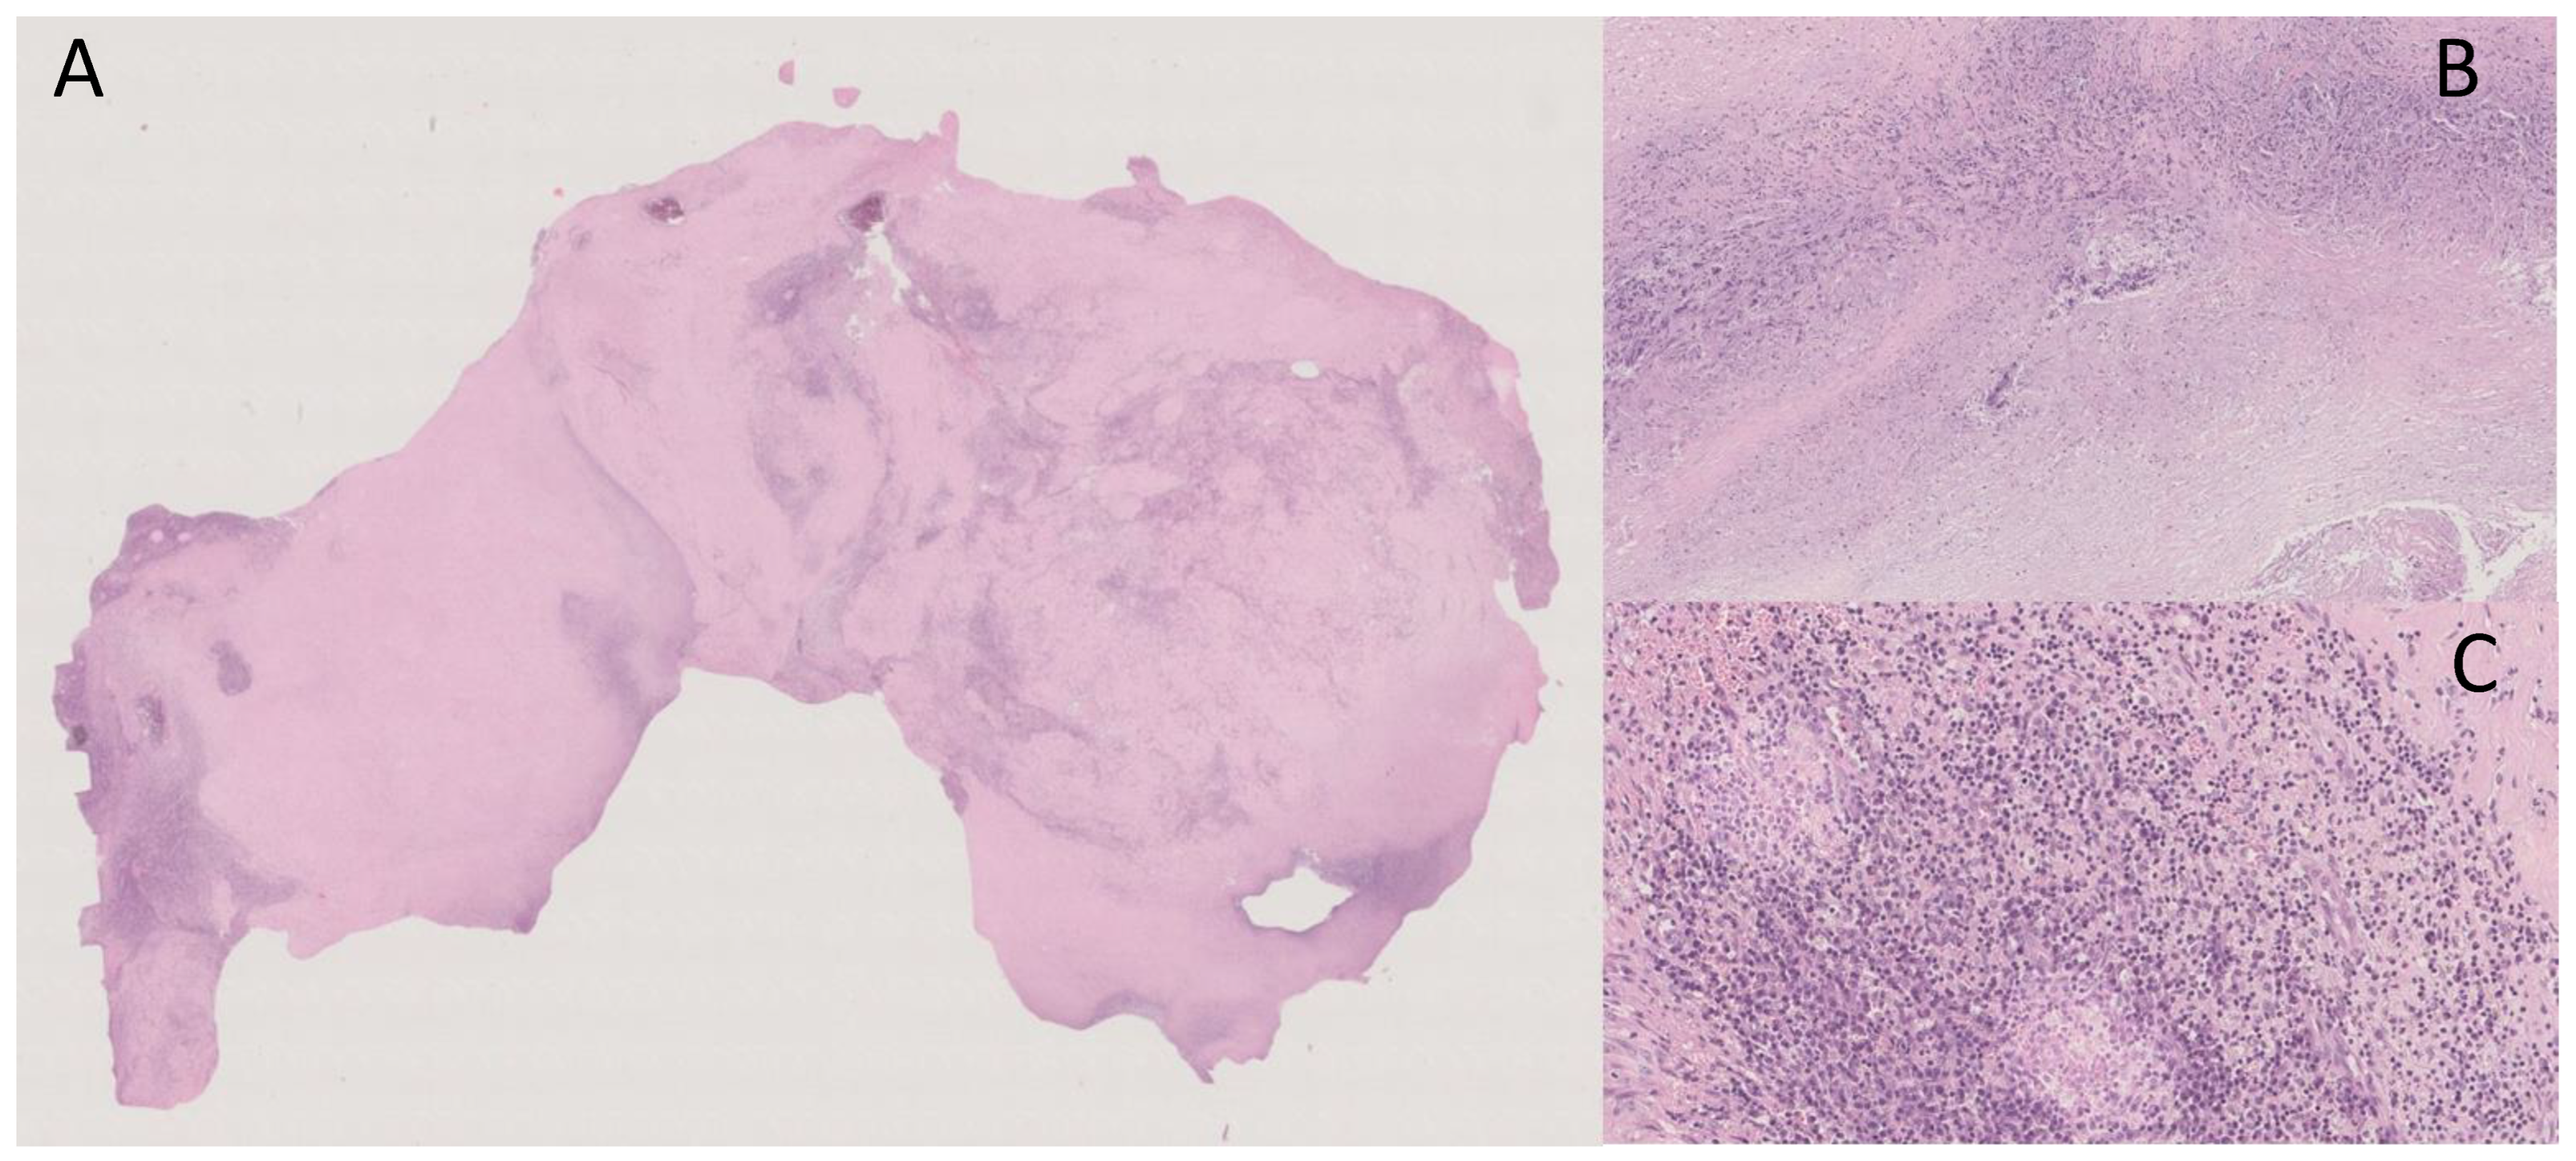

A subsequent positron emission tomography–computed tomography (PET-CT) scan revealed the presence of diffuse and pathological accumulation of the radiotracer (max SUV 13.6) in correspondence with the lymphatic nodules seen in magnetic resonance imaging (MRI) (Figure 2).

Figure 2.

Coronal MRI (left), CT (middle) and PET (right) scans showing the presence, in mesogastrium, of a nodular mass (red arrows) with contrast enhancement at MRI and internal calcifications at CT, with thickened mesenterial fat and significant uptake of the radiotracer at PET-CT.